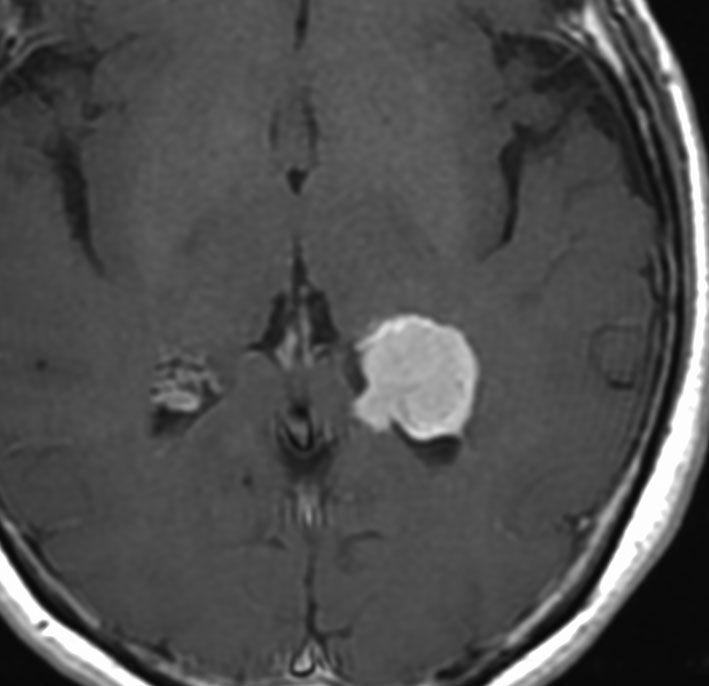

30代の女性に発生した髄膜腫です,一見すると松果体細胞腫と見分けはつきません。右の画像に見られるように典型的な中脳水道狭窄を生じていました。

軽度の閉塞性水頭症もありますが,頭痛も無く無症状なので経過を観察しました。髄膜腫だと診断できるのは,右の画像で見られるようにガレン大静脈が右側に偏っているからです。松果体細胞腫の場合は,ガレン大静脈は上方に変位します。

1年間経過観察したら水頭症が進行して脳室が拡大,腫瘍のサイズも大きくなりました。右側の画像で見られるようにガレン大静脈の左側のテントの下面から発生した髄膜腫でした。

左は手術直後の画像です,手術は左側のテント下面を見るために,後頭部経テント法 OTA occipital transtentorial approach で,小脳テントの左側を切断して腫瘍を全摘出しました。右側は6年後の画像ですが,腫瘍再発はありません。